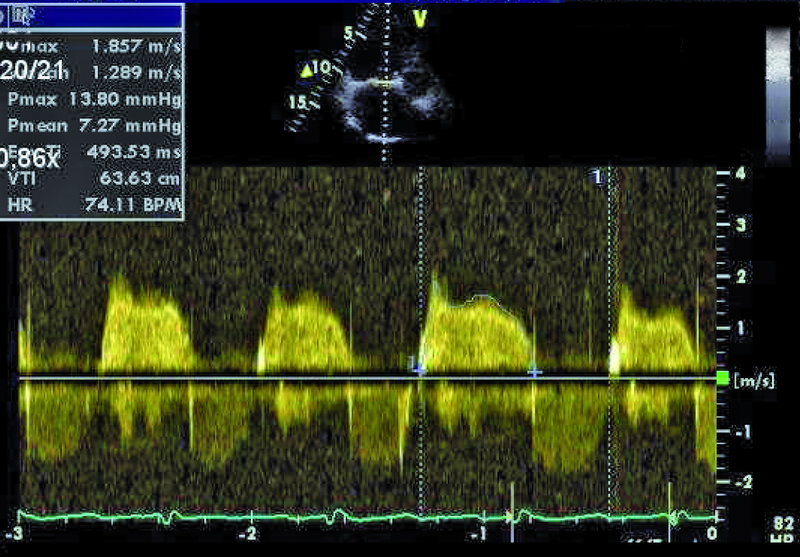

Szczegóły oceny układu krążenia z okresu przeprowadzanych operacji nie były znane. Można było jedynie przypuszczać, że śluzak prawej komory mógł zaburzać funkcję zastawki trójdzielnej, a jego resekcja pozostawiła stopniowo narastającą nieszczelność zastawki. Wymiana zastawki na biologiczną była konieczna, ale spowodowała dalsze problemy u chorego. Degeneracja zastawek biologicznych u osoby młodej może postępować dynamicznie, nawet bez obecności dodatkowych czynników nasilających to zjawisko, jak niewydolność nerek czy nadczynność przytarczyc. Kolejnym czynnikiem, poza wiekiem, wpływającym na odpowiedź immunologiczną, może być samo ujście trójdzielne, w którym procesy wapniowo-fosforanowe w odpowiedzi na rozciąganie płatków są silne. Warto także nadmienić, że zastawki biologiczne stentowe, jak użyta w tym wypadku, charakteryzują się szybszym tempem zwyrodnienia niż zastawki bezstentowe. Rozpoznanie strukturalnego zwyrodnienia bioprotezy w ujściu trójdzielnym nie powinno nastręczać trudności. Wczesnymi objawami procesu jest pogrubienie i usztywnienie płatków, które stają się w obrazie ultradźwiękowym jaśniejsze i nieregularne w zarysie (ryc. 1, 2). Ponieważ proces postępuje, włóknienie i zwapnienia obejmują najpierw spoidła, a następnie całe płatki i pierścień zastawki. W przedstawionym przypadku zwyrodnienie prowadzi zarówno do stenozy, jak i niedomykalności. O stenozie zastawki w ujściu trójdzielnym zawsze należy myśleć, gdy gradient średni napływu przekracza 6 mm Hg (ryc. 3). Niedomykalność trójdzielna uważana jest za istotną, kiedy talia strumienia ma szerokość co najmniej 6 mm (ryc. 4). Warto dodać, że rejestrowane zmiany hemodynamicznie są podobne do tych, jakie obserwuje się w natywnej zastawce trójdzielnej np. w rzadkim uszkodzeniu poreumatycznym. Chory ma wskazania do kolejnej interwencji kardiochirurgicznej i operacja w tym wypadku nie powinna być odkładana, żeby nie doprowadzić do narastającej niewydolności jam prawego serca. By uzupełnić ocenę, zarejestrowano projekcję na drogę odpływu prawej komory (ryc. 5). Wykluczono cechy nadciśnienia płucnego i niedomykalność zastawki płucnej. Zwrócono uwagę na istotnie poszerzone jamę prawego przedsionka i żyłę główną dolną (ryc. 6), odpowiadające nieprawidłowościom w badaniu fizykalnym – hepatomegalii i obrzękom obwodowym. Poza operacją można rozważyć wykonanie zabiegu techniką przezcewnikową i wszczepienie zastawki Edwards SAPIEN lub Melody (valve-in-valve). W tym wypadku na decyzji o leczeniu operacyjnym zaważyły jednak preferencja chorego i doświadczenie ośrodka.